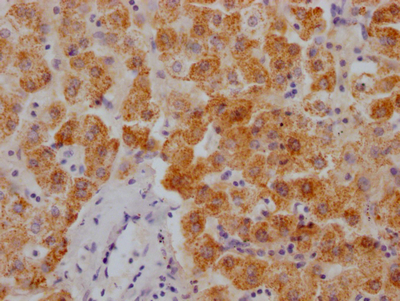

IHC image of CSB-RA172058A0HU diluted at 1:100 and staining in paraffin-embedded human prostate cancer performed on a Leica BondTM system. After dewaxing and hydration, antigen retrieval was mediated by high pressure in a citrate buffer (pH 6.0). Section was blocked with 10% normal goat serum 30min at RT. Then primary antibody (1% BSA) was incubated at 4°C overnight. The primary is detected by a Goat anti-rabbit polymer IgG labeled by HRP and visualized using 0.05% DAB.

IHC image of CSB-RA172058A0HU diluted at 1:100 and staining in paraffin-embedded human kidney tissue performed on a Leica BondTM system. After dewaxing and hydration, antigen retrieval was mediated by high pressure in a citrate buffer (pH 6.0). Section was blocked with 10% normal goat serum 30min at RT. Then primary antibody (1% BSA) was incubated at 4°C overnight. The primary is detected by a Goat anti-rabbit polymer IgG labeled by HRP and visualized using 0.05% DAB.